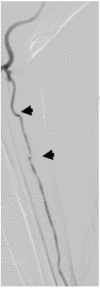

Unfavorable Vascular Anatomy during Endovascular Treatment of Stroke: Challenges and Bailout Strategies

The benefit of mechanical thrombectomy (MT) in acute ischemic stroke (AIS) due to large vessel intracranial occlusions is directly related to the technical success of the procedures in achieving fast and complete reperfusion. While a precise definition of refractoriness is lacking in the literature, it may be considered when there is reperfusion failure, long procedural times, or high number of passes with the MT devices. Detailed knowledge about the causes for refractory MT in AIS is limited; however, it is most likely a multifaceted problem including factors related to the vascular anatomy and the underlying nature of the occlusive lesion amongst other factors. We aim to review the impact of several key unfavorable anatomical factors that may be encountered during endovascular AIS treatment and discuss potential bail-out strategies to these challenging situations.